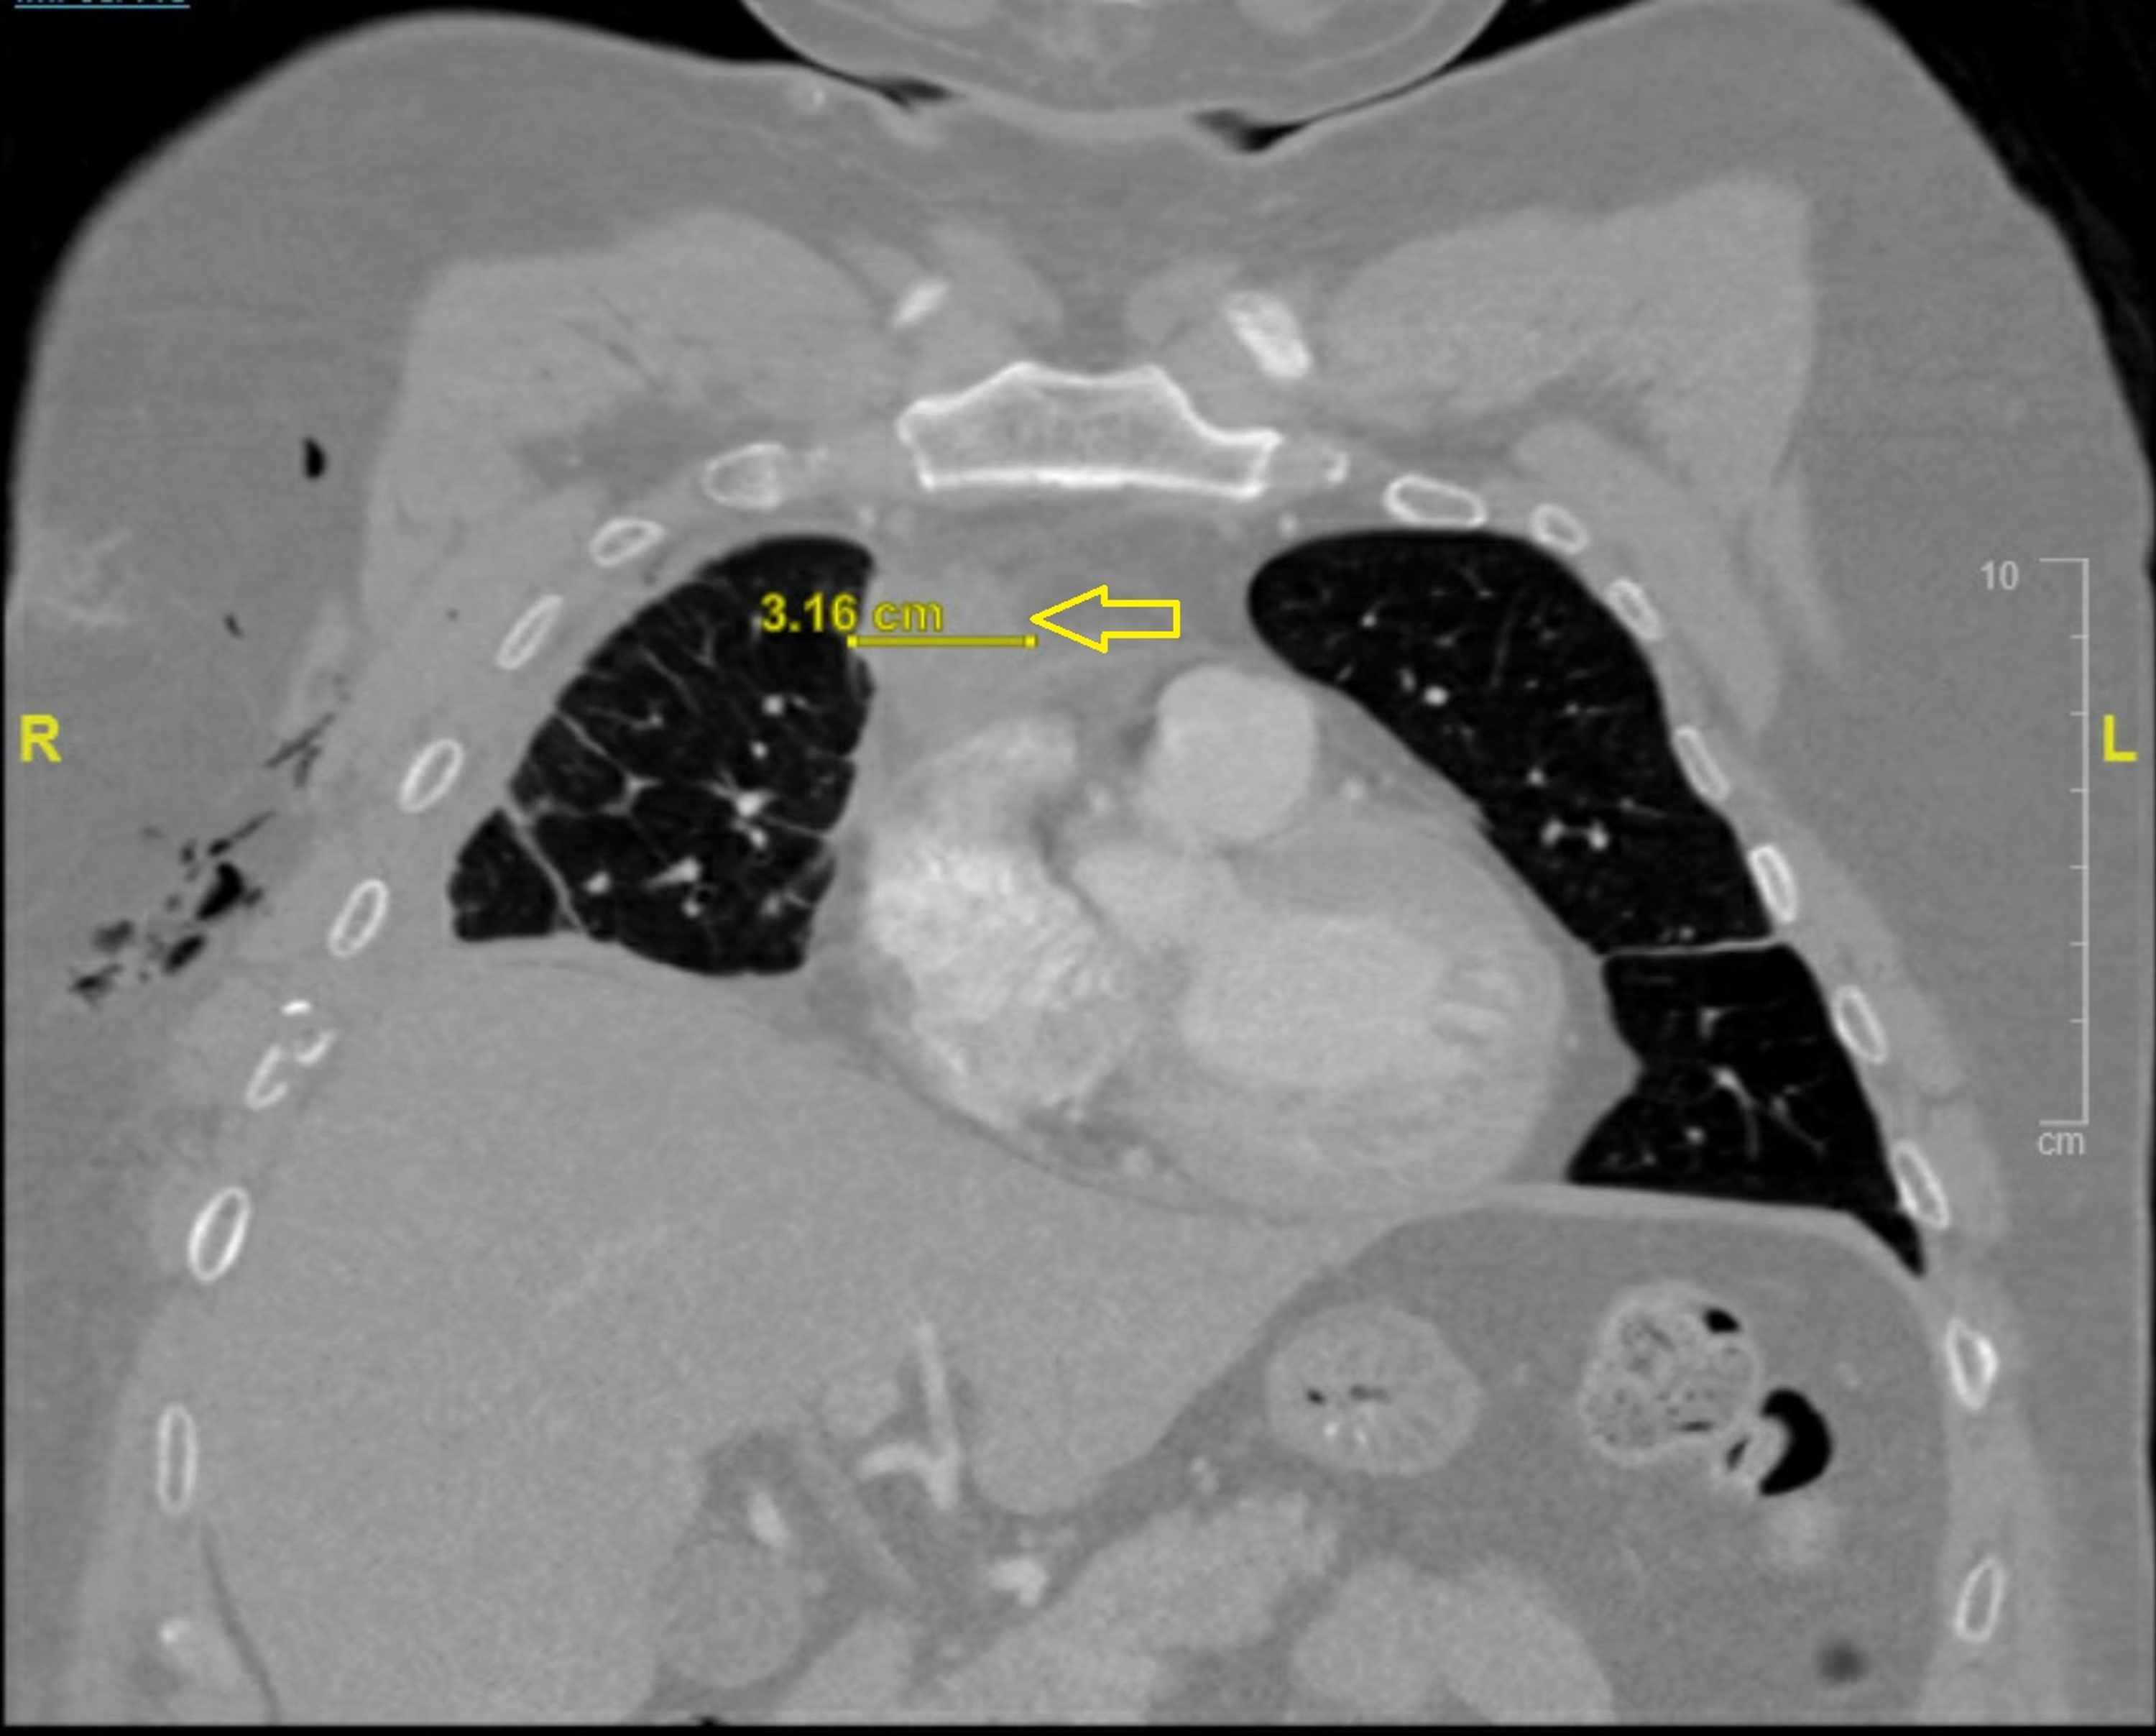

Baseline imaging of the primary thymic neuroendocrine tumor. CT axial Thymic Neuroendocrine Tumor Although clinical and molecular data are sparse, their general. The latest world health organization (who) classification from 2015 has grouped lung and thymic neuroendocrine tumours (nets) (named neoplasm in the digestive who classification) within one unique group but confirmed their subdivision into four main categories: Primary neuroendocrine tumors of the thymus (netts) are rare and biologically. Thymic neuroendocrine tumors (nets). Thymic Neuroendocrine Tumor.